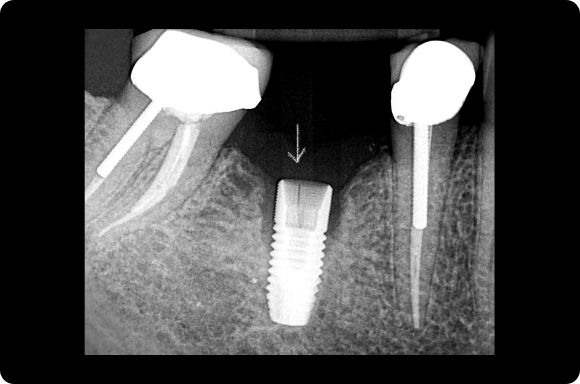

This mastery-level course discusses both the prevention and management of surgical and restorative complications. Within the surgical realm, the presentation focuses on early implant failure and later peri-implant disease. Prosthetic concepts will involve preventative prosthesis design, screw/abutment removal, and sequencing that acknowledges the importance of patient experience.

The implant curriculum is an interactive, procedure-based series of courses that use individual cases to teach current implant treatment. This approach is in contrast to conventional dental education that focuses more on didactic topics and theory. The purpose of using this educational approach is to highlight the patients and procedures found in everyday clinical practice, where the most important concepts are observed and discussed in multiple clinical scenarios.